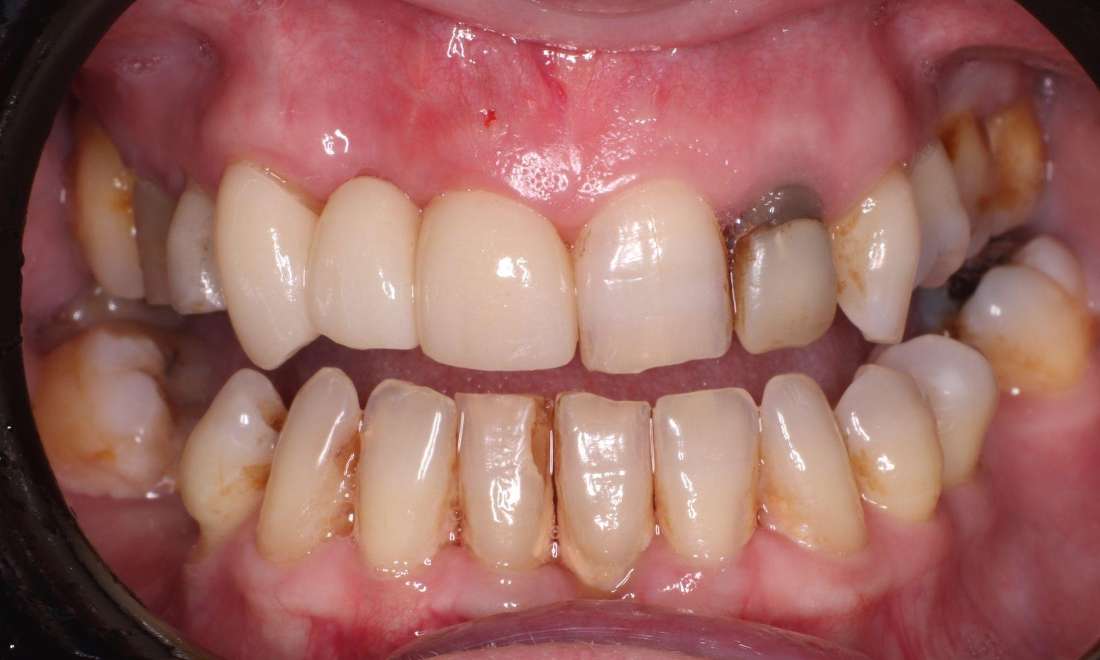

One of our patients came to us with a missing tooth and reported feeling self-conscious about their smile. We recommended a dental bridge to restore both function and aesthetics. Anchored to the surrounding teeth, the bridge provided a strong, reliable and natural-looking solution. After treatment, they could smile confidently and enjoy their favourite foods without discomfort.